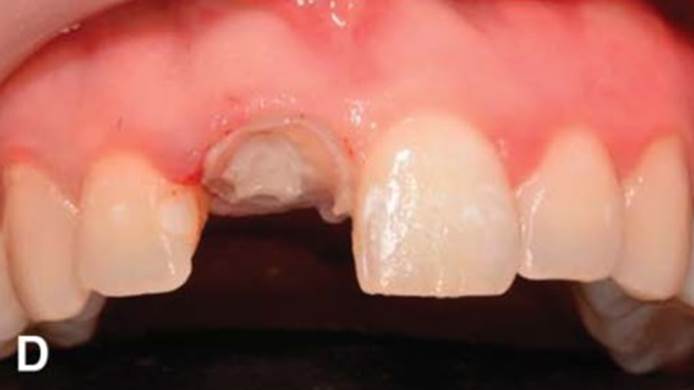

Clinical case: Replacement of fractured central incisor (#11) with immediate implant

& Root Membrane Technique

- Courtesy of Dr. Miltiadis Mitsias, Greece -

AnyRidge, Root Membrane Technique, retrospective study, long-term study, immediate implants, bone resorption, bone preservation, Dr. Miltiadis Mitsias,survival, success, maxillary anterior, single replacement

AnyRidge implant system, Root Membrane kit

The Root Membrane Technique: A retrospective clinical study with up to 10 years of follow-up./Implant Dent. 2018 Oct;27(5):564-574

https://www.ncbi.nlm.nih.gov/pubmed/30161062